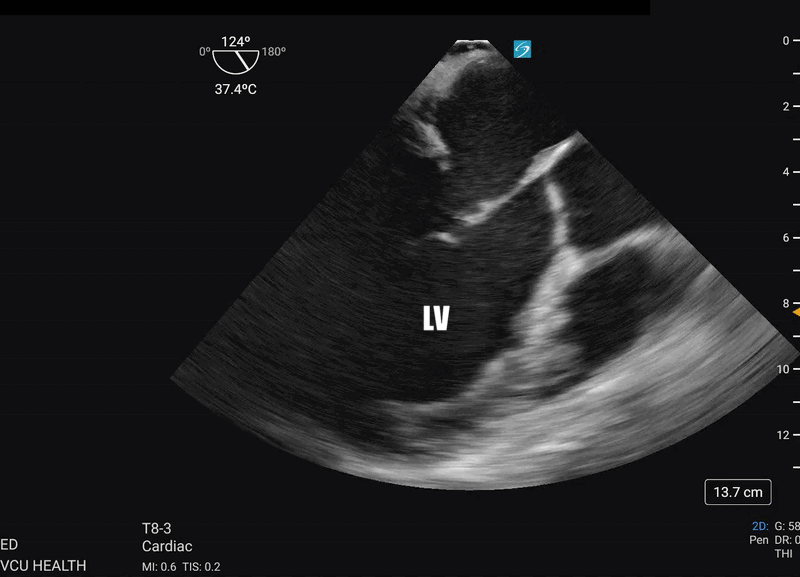

Most importantly for the resuscitationist, the ME-LAX view is used to evaluate the quality of CPR and hand placement for chest compressions; so it should be obtained during initiation of CPR and even when changing CPR providers if possible. Optimal chest compressions should result in vigorous LV squeeze with near concurrent aortic valve opening (Figure 2). Incorrect compressions, usually too high on the chest wall, will result in LV outflow obstruction and ineffective CPR (Figure 3). This can be seen on the ME-LAX view as squeeze over the AV itself, narrowing of the aortic outflow tract, absence of LV compression and/or absence of aortic valve opening during compressions. Signs of ineffective CPR should prompt adjustments in compression location and/or depth and subsequent re-evaluation for effectiveness.2

Figure 2. Me-LAX view during CPR (slowed to 50% speed) showing mid-LV compression with concurrent aortic valve opening